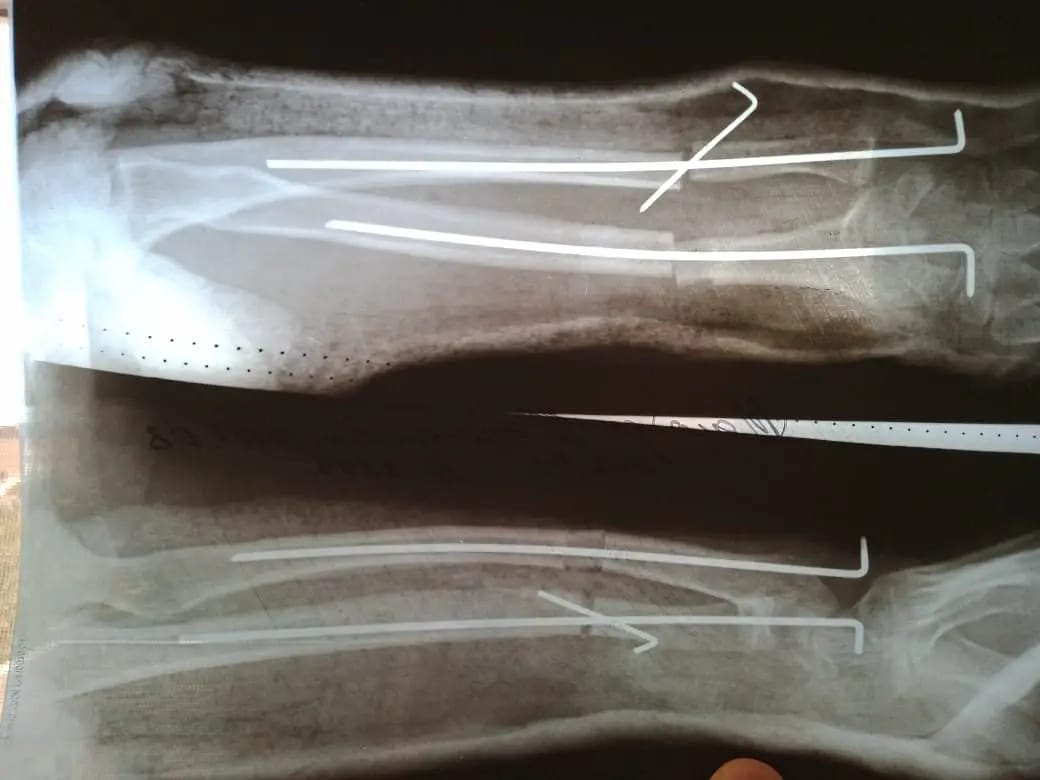

Науқас осыдан бірнеше жыл бұрын қолын ауыр жарақаттап, шынтақ сүйегі өсіп, кәрі (лучевая) сүйегі өспей қалған. Салдарынан қолындағы сүйектері қисайып, өздігінен қимыл жасауға кедергі келтірген.

«Ота жасалған науқас үш ай бұрын қалалық клиникалық балалар ауруханасына кеңес алуға келген болатын. Тексере келе науқаста жарақаттың салдарынан сүйегі қисайғаны анықталды. Операцияны бірден жасамадық. Себебі мұндай ота баланың сүйек өсуі тоқтауға жақындаған кезде жасалады. Операция кезінде қатты өсіп кеткен сүйекті қысқартып, өспей қалған сүйекке жалғап, арнайы құрылғымен бекітіп бердік. Мұндай отаны бірінші рет жасадық. Осыған дейін сүйегі қисық өскен науқастарға ота жасау үшін Нұр-Сұлтан қаласындағы емдеу мекемелеріне жолдама арқылы жіберетінбіз. Енді міне мұндай отаны өзіміз жасауға дайынбыз» дейді ортопед-травматолог Бағжан Тұрдықұлов.